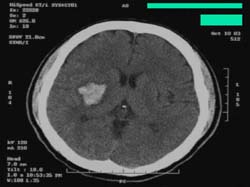

<Áß´ë³úµ¿¸Æ

ÁÖÁÙ±âÀÇ ³ú°æ»ö> <°æ¸·ÇÏ

Ç÷Á¾ÀÇ ¼ö¼ú ÈÄ CT>

<³úÃâÇ÷ÀÇ

CT>